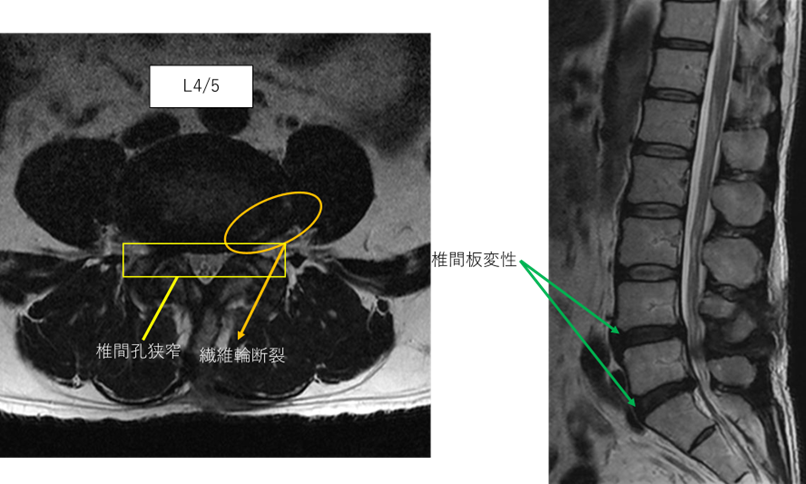

L1/2: 異常なし

L2/3: 異常なし

L3/4: 異常なし

L4/5: 椎間板変性症、両椎間孔狭窄、繊維輪断裂

L5/S: 椎間板変性症、繊維輪断裂

以上の事が画像上認められます。

L4/5、5/sに

椎間板変性症、両椎間孔狭窄、繊維輪断裂を認め、主症状の原因の可能性が高い。